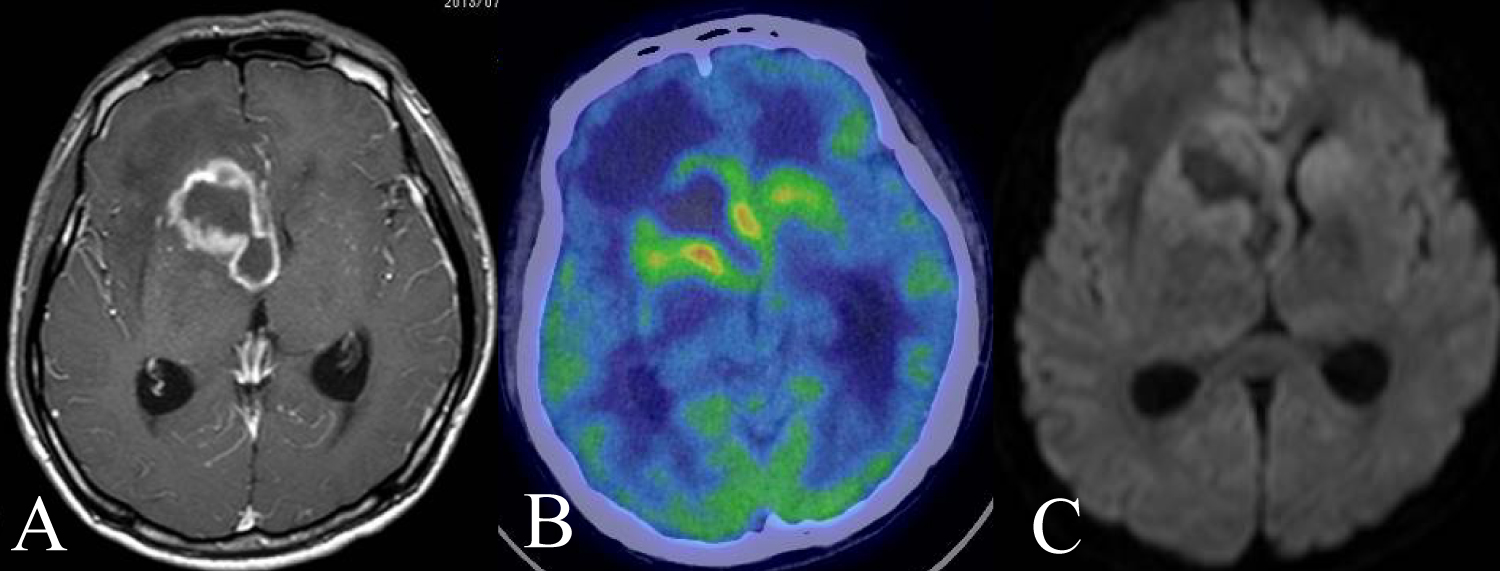

A 42-year-old man presented headache and left hemiparesis of lower limb, and came to our office. We diagnosed his AIDS at 29-year-old and he had been given combined antiretroviral therapy (ART). Contrast MRI showed a ring enhancement lesion in right frontal lobe (Figure 1A). FDG-PET showed central low uptake and moderate uptake at tumor rim (Figure 1B). Meanwhile, diffusion weighted imaging (DWI) showed no clear findings (Figure 1C). At first, we suspected toxoplasmosis and performed stereotactic biopsy. The histopathological findings were diffuse large B cell lymphoma (DLBCL) against our expectations. We performed whole brain radiotherapy as adjuvant therapy. Due to low CD4 positive T cell in number, we could not induce chemotherapy. Although we expected his severe prognosis, he survives at 145 months.

Figure 1: A) A 42-year-old man presented headache and left hemiparesis of lower limb. Contrast MRI showed a ring enhancement lesion in right frontal lobe; B) FDG-PET showed central low uptake and moderate uptake at tumor rim; C) DWI showed only edematous findings. Although we suspected toxoplasmosis at first, the histopathological findings were DLBCL. View Figure 1